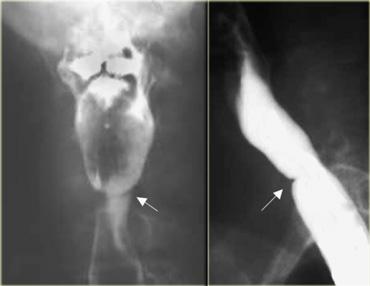

Achalasia cơ nhẫn hầu ở phụ nữ 46 tuổi. Cảm giác có khối vướng ở cổ họng. Ấn lõm dai dẳng (mũi tên) do cơ nhẫn hầu không giãn ra khi khối thức ăn di chuyển xuống phía dưới

Cơ thắt thực quản trên

- Được tạo thành chủ yếu bởi cơ nhẫn hầu.

- Nằm ở mức C5-C6

- Bình thường giãn ra khi có khối thức ăn đi qua

- Các bất thường

- Giãn chậm

- Đóng sớm

- Không giãn: có hoặc không có triệu chứng; nếu có triệu chứng, được gọi là achalasia cơ nhẫn hầu